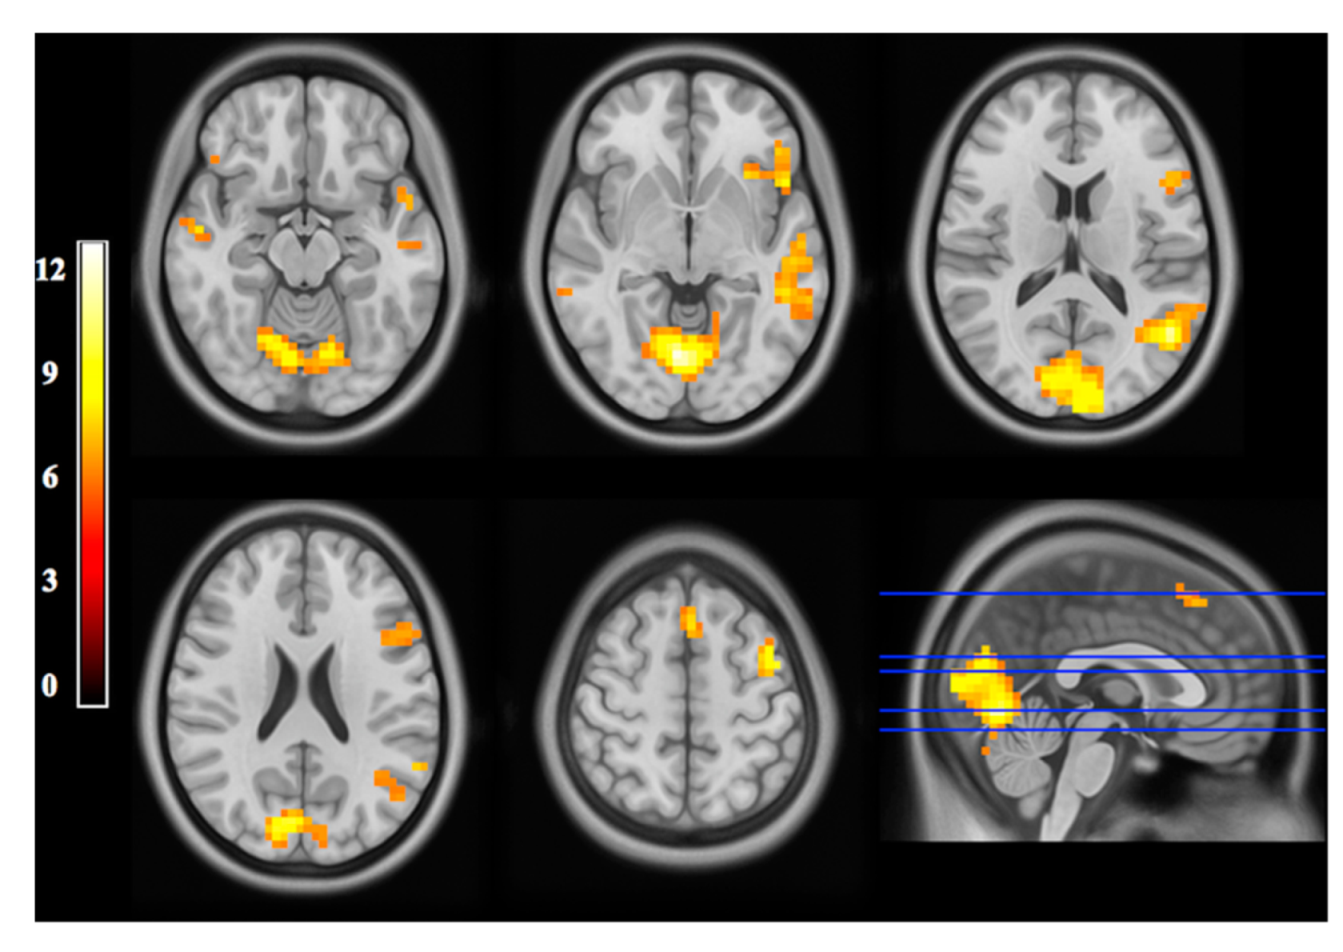

- Pechenkova, E.; Nosikova, I.; Rumshiskaya, A.; Litvinova, L.; Rukavishnikov, I.; Mershina, E.; Sinitsyn, V.; Van Ombergen, A.; Jeurissen, B.; Jillings, S.; et al. Alterations of Functional Brain Connectivity After Long-Duration Spaceflight as Revealed by FMRI. Front. Physiol. 2019, 10, 761. [Google Scholar] [CrossRef]

- Demertzi, A.; Van Ombergen, A.; Tomilovskaya, E.; Jeurissen, B.; Pechenkova, E.; Di Perri, C.; Litvinova, L.; Amico, E.; Rumshiskaya, A.; Rukavishnikov, I.; et al. Cortical Reorganization in an Astronaut’s Brain after Long-Duration Spaceflight. Brain Struct. Funct. 2016, 221, 2873–2876. [Google Scholar] [CrossRef] [Green Version]